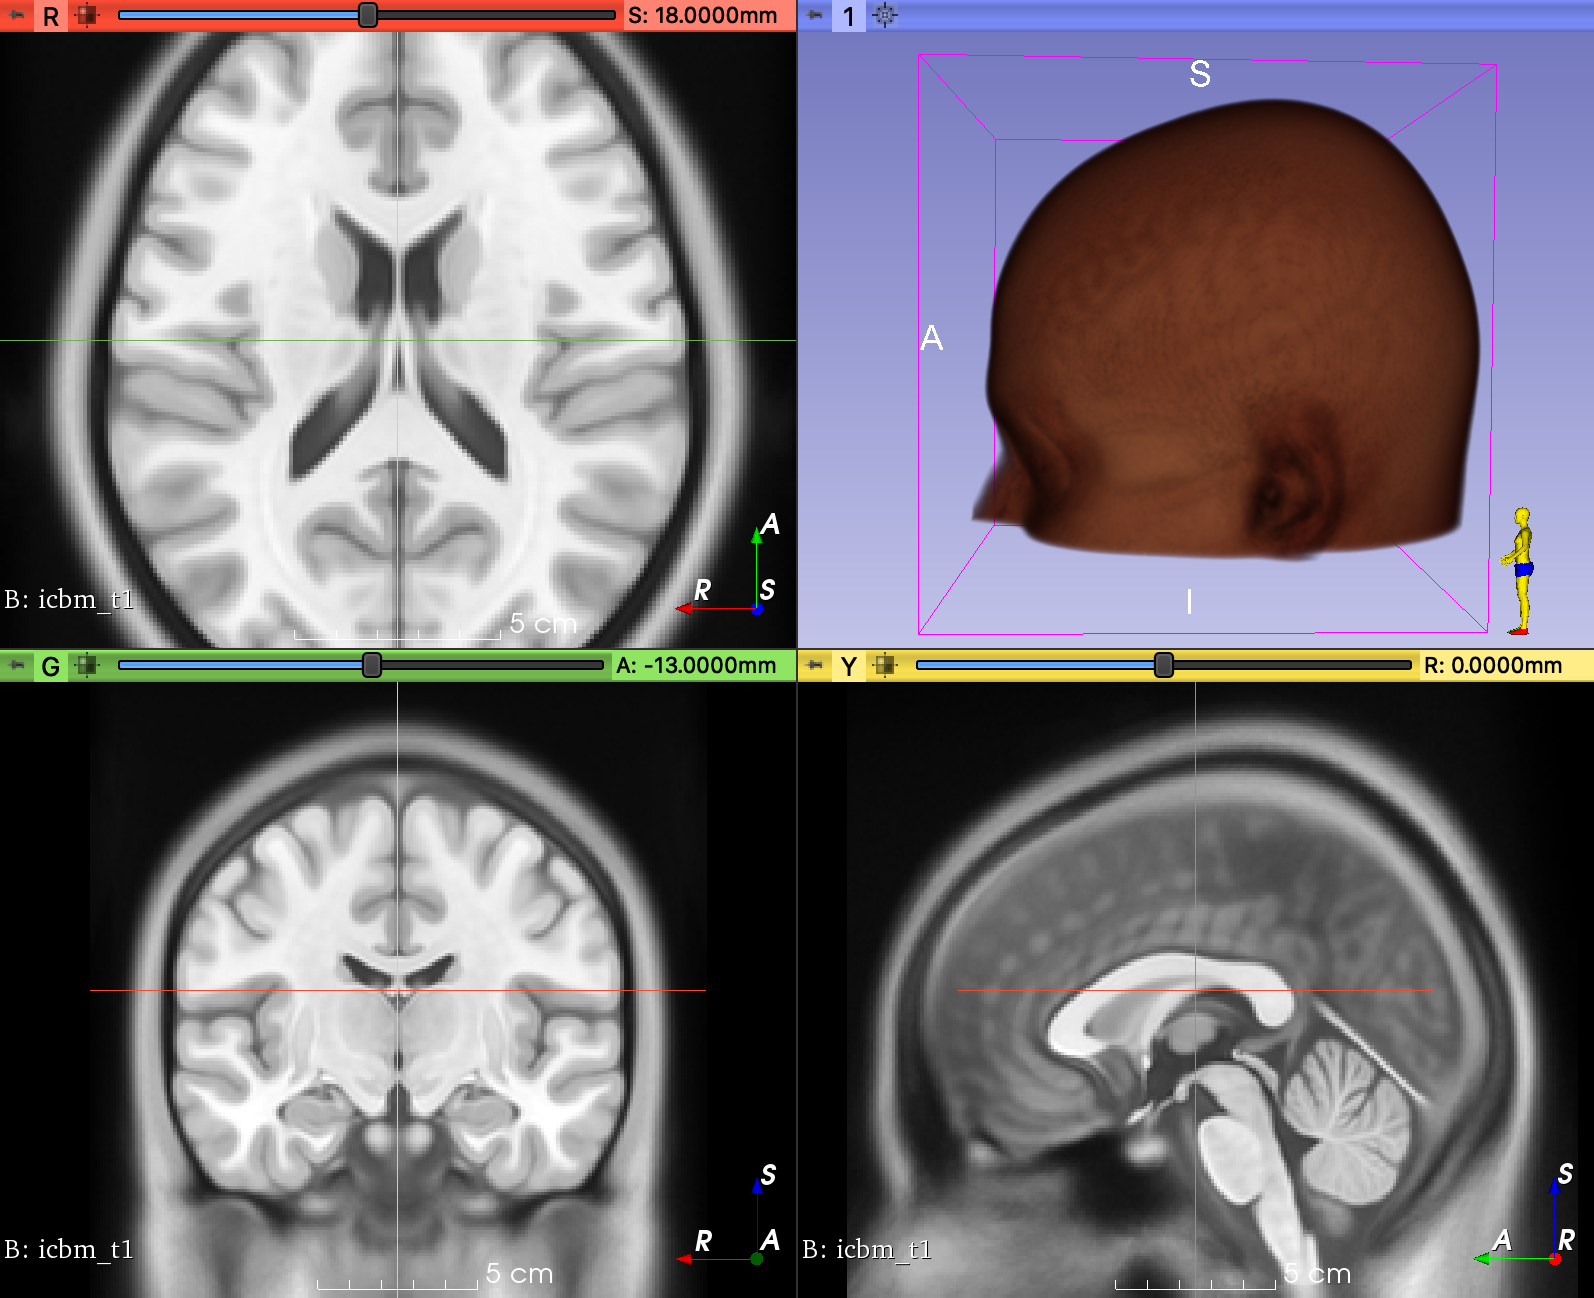

The docs for

Therefore, it should work if you do something like: subject_a = tio.Subject(image=tio.ScalarImage(["A.jpg", "B.img"])) |

Imagesay:Therefore, it should work if you do something like: